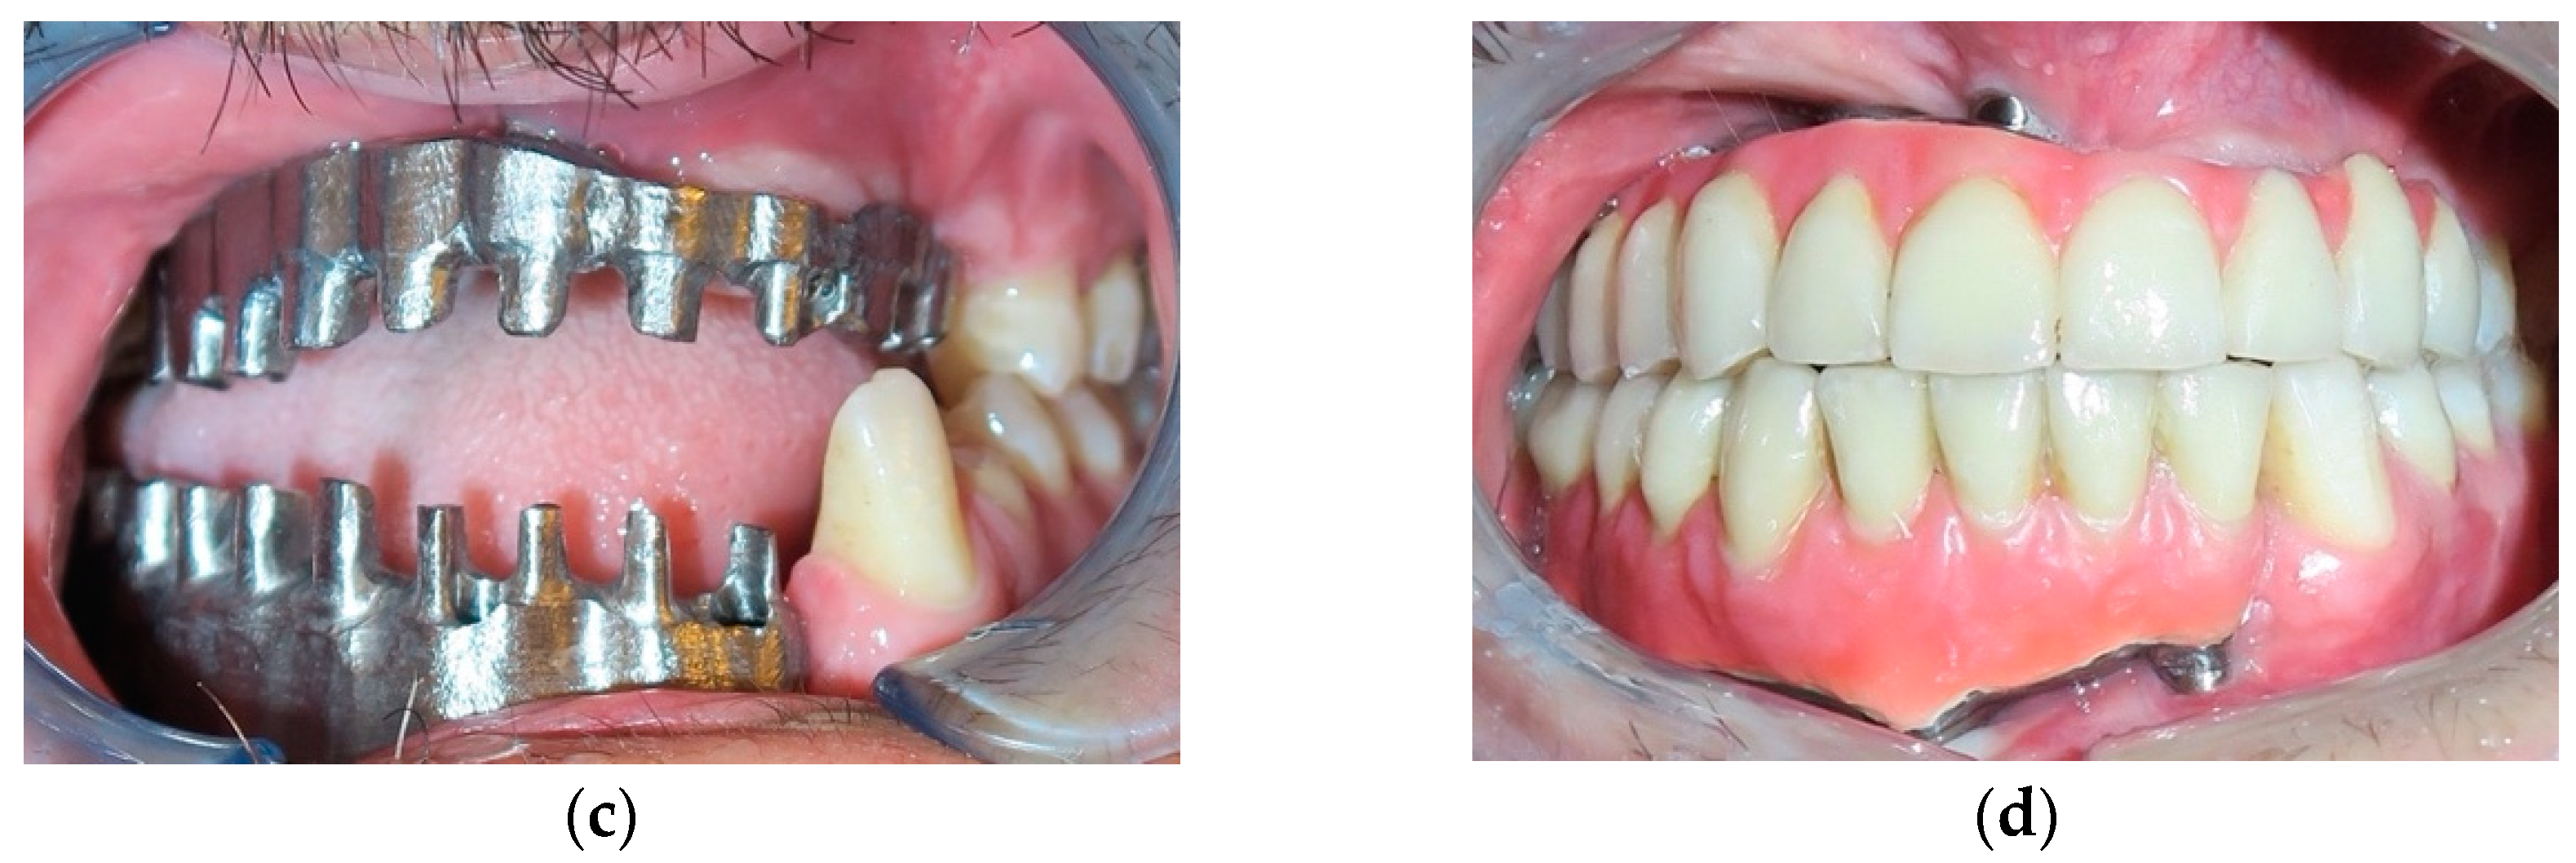

| 1 | 22/M | High-velocity injury | T4, Lower maxilla, Basal bone, Gingival tissue and Soft tissue | Emimandibulectomy dx | Free Fibula Flap | Fixed implant-supported prosthesis (n. 5 dental implants) |

| 3 | 29/M | High-velocity injury | T4, Upper maxilla, Basal bone, Gingival tissue and Soft tissue | Emimaxillectomy dx | Free Fibula Flap | Fixed implant-supported prosthesis (n. 6 dental implants) |

| 4 | 31/M | High-velocity injury | T4, Upper and Lower maxilla, alveolar bone, Gingival and Soft tissue | Alveolar Resection, I quad. + IV quad. | Free Iliac Crest Flap | Fixed implant-supported prosthesis (n. 10 dental implants) |